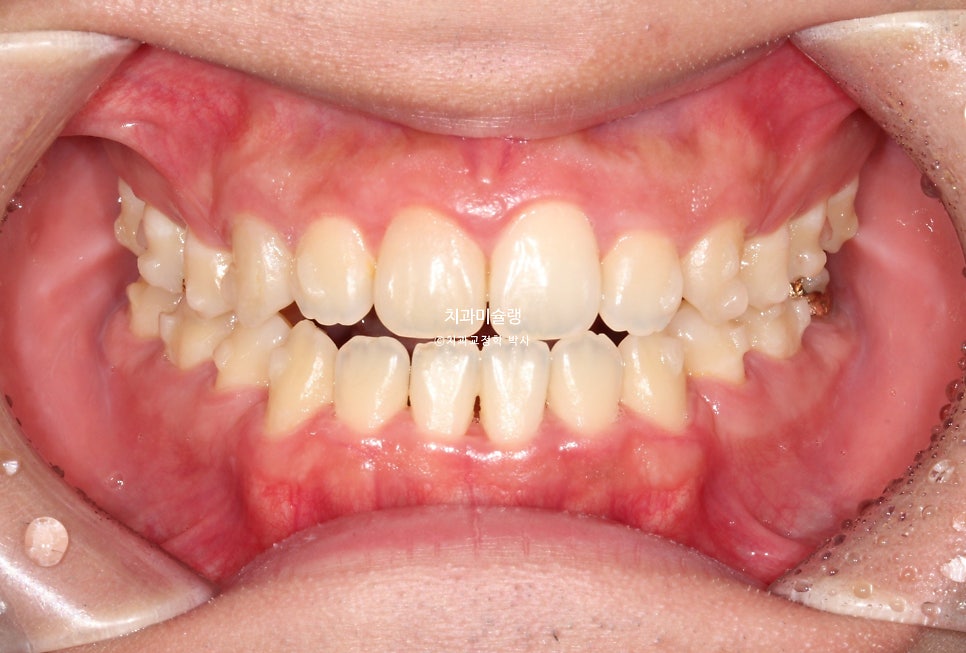

2026년 2월 치료 완료

중심선은 정확히 맞으며 앞니 교합은 좋습니다.

어금니 교합은 물샐틈 없는 1급 교합관계를 보입니다.

치료 결과 비교

이제 전후 비교 볼게요.

총 치료기간은 2년이 채 안걸린 1년 11개월 이며 총 내원 횟수는 10회 입니다.